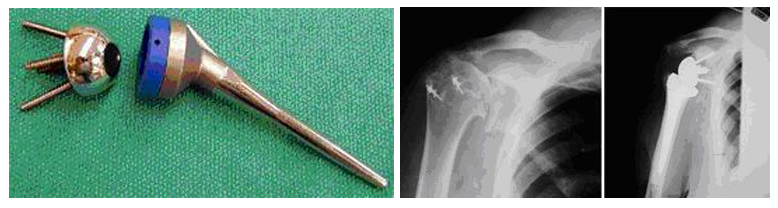

• Hemiarthroplasty – Half Shoulder Replacement

The usual total shoulder replacement involves replacing the arthritic joint surfaces with a highly polished metal ball attached to a stem, and a plastic socket.

Depending on the condition of the shoulder, your surgeon may replace only the ball. Sometimes, this decision is made in the operating room at the time of the surgery. Some surgeons replace the ball when it is severely fractured and the socket is normal.